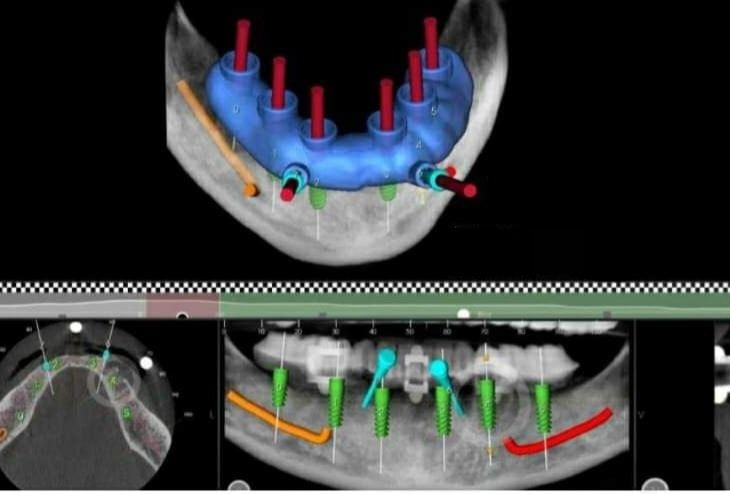

L’implantologia dentale è una branca dell’odontoiatria che ha l’obiettivo di ripristinare i denti mancanti mediante l’inserimento di radici artificiali in titanio (impianti dentali).